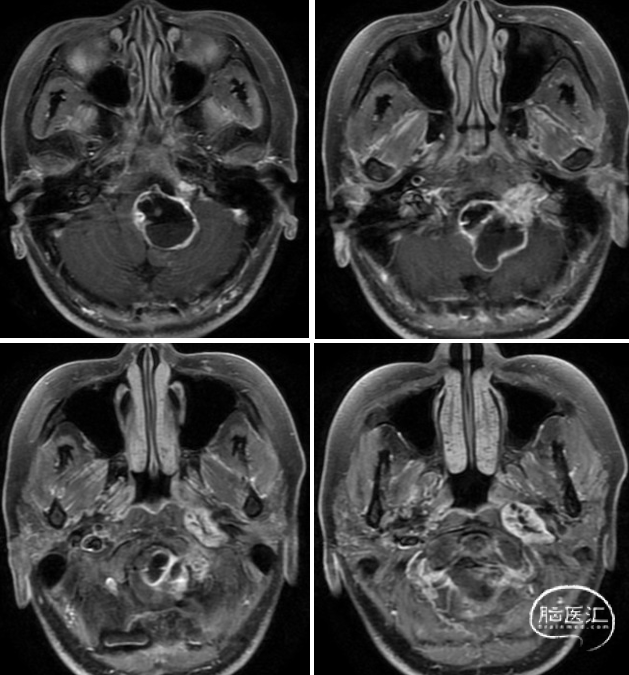

术中情况

左:磨除髁旁及髁上部分骨质暴露颈静脉孔区,右:切除颈静脉孔内部分肿瘤

左:剪开乙状窦后方硬膜并与颈静脉孔贯通,右:剪开肿瘤贯穿处硬膜环

左:切除颈静脉孔内肿瘤,右:暴露载瘤神经近端并剪断

左:分离肿瘤与副神经之间黏连,右:进一步分离肿瘤

左:分离载瘤神经远端并剪断,右:全切肿瘤

术后影像

术后MRI显示肿瘤切除满意